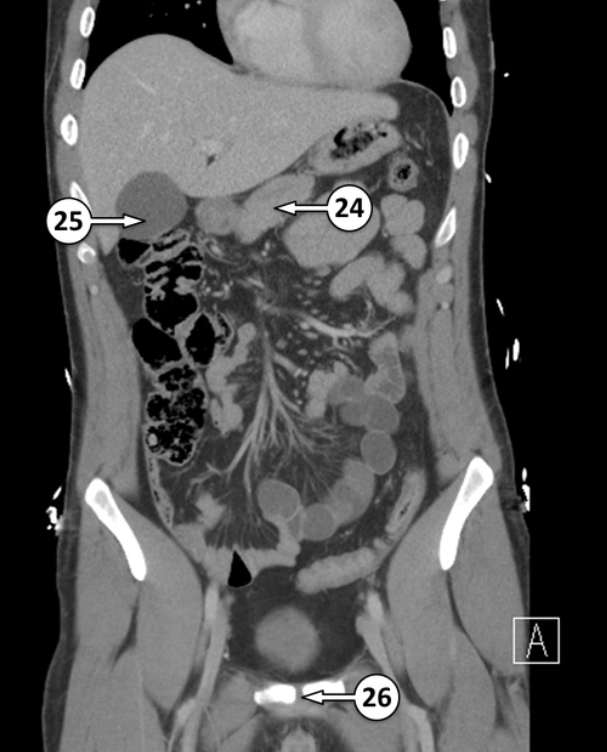

Label 25 and 26

Common hepatic duct

Segment VI of the liver